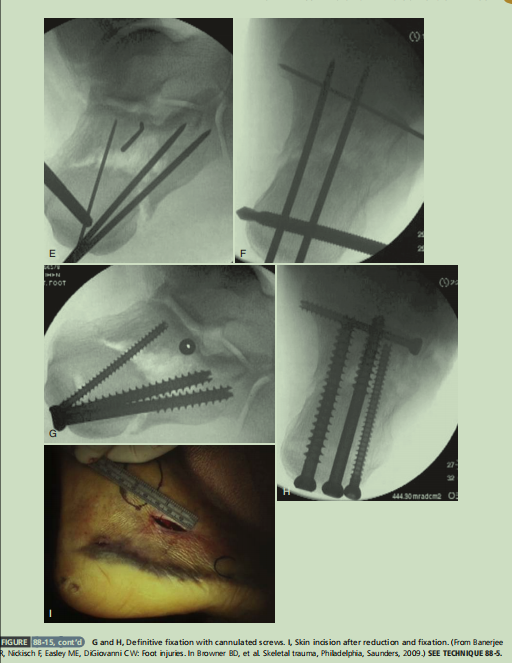

大L型切口,克氏针牵拉撬拨复位内翻畸形,D图的临时克氏针固定内翻畸形这个技巧很重要,最后复位关节面。F、G图显示术后透视可见解剖复位。